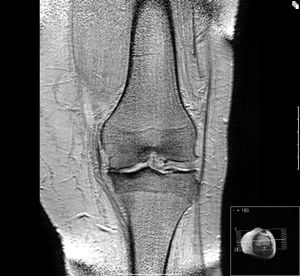

골관절염은 관절 연골의 손상과 퇴행을 특징으로 하는 흔한 관절 질환이다. 통증, 뻣뻣함, 관절 운동 시 삐걱거리는 소리, 관절 잠김 등의 증상이 나타나며, 손, 발, 척추, 엉덩이, 무릎 등 체중 부하가 큰 관절에 주로 발생한다. 노화, 관절 부상, 비만 등이 주요 원인이며, 일차성과 이차성으로 분류된다. 진단은 병력 청취, 신체 검사, X-ray 촬영을 통해 이루어진다. 치료는 통증 완화와 관절 기능 개선을 목표로 하며, 생활 습관 개선, 진통제, 비스테로이드성 소염 진통제(NSAIDs) 등이 사용된다. 심한 경우 수술적 치료(관절경 수술, 인공 관절 치환술 등)를 고려할 수 있으며, 제대혈 줄기세포 치료법과 같은 연구도 진행 중이다. 전 세계적으로 무릎 골관절염 환자는 약 2억 5천만 명으로 추정되며, 다양한 동물 종에서도 발생한다.

5. 진단

뼈관절염의 진단은 병력 청취 및 신체 검사를 통해 이루어지며, X-ray 촬영으로 확진할 수 있다.[52][53][54] X-ray 소견으로는 관절 간격 협소, 연골하 경화증(관절 주위 뼈 형성 증가), 연골하 낭종 형성, 골극 형성이 나타난다.[54] 다만, 단순 촬영 소견은 신체 검사 소견이나 통증 정도와 일치하지 않을 수 있다.[55]